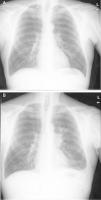

Nueve meses más tarde comenzó con tos y expectoración, sin mejoría tras antibioterapia. Se evidenció en radiografía de tórax una masa hiliar izquierda con diagnóstico anatomopatológico por biopsia transbronquial de carcinoma microcítico. La TAC mostró múltiples implantes tumorales pleurales, hepáticos y conglomerados adenopáticos paratraqueales y subcarinales (fig. 1). Ante este diagnóstico, se retira la inmunosupresión y se inicia tratamiento con carboplatino-etopósido, que no evita el empeoramiento clínico progresivo y el fallecimiento un mes después.